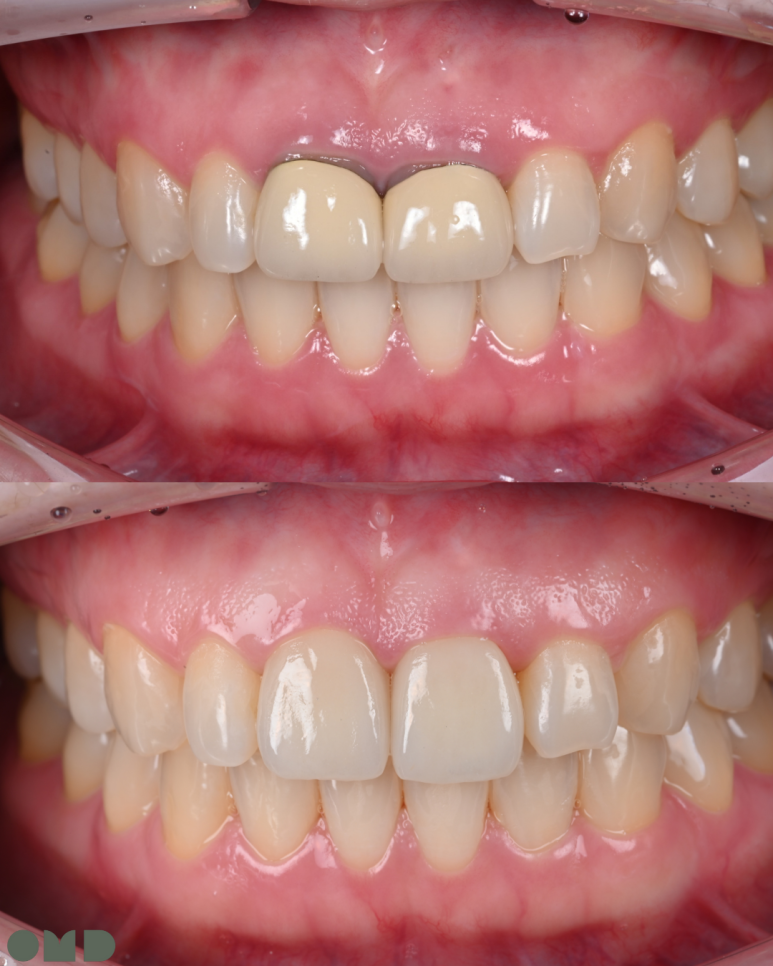

약 3주의 기간 동안 크라운 주변 잇몸이 잘 적응한 것을 확인 할 수 있었습니다.

25.08.11 임시치아 장착

25.09.04 임시치아 장착 약 3주 후

5. 최종 크라운 장착

새로 제작된 크라운을 장착합니다.

환자분께서 색상과 모양에 만족해하셔서 특별한 수정없이

치료를 마무리할 수 있었습니다.

25.09.11 치료 후